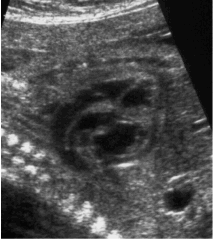

La Ecocardiografía Fetal es la ciencia que, mediante el uso de la ecografía, nos permite diagnosticar la mayor parte de las alteraciones del sistema cardiovascular del bebé dentro del vientre materno. Mediante una inocua ecografía, similar a las realizadas en las embarazadas durante su seguimiento obstétrico pero centrada en el corazón, es posible dar un diagnóstico y muchas veces el pronóstico de la anomalía congénita más frecuente: las alteraciones cardíacas.

A partir de las 18-20 Semanas de gestación ya podemos vislumbrar la mayoría de las partes del corazón con cierta eficacia, a pesar de que el 100% de las alteraciones cardíacas no se pueden descartar por las peculiaridades de la fisiología de la circulación del corazón dentro del útero materno.